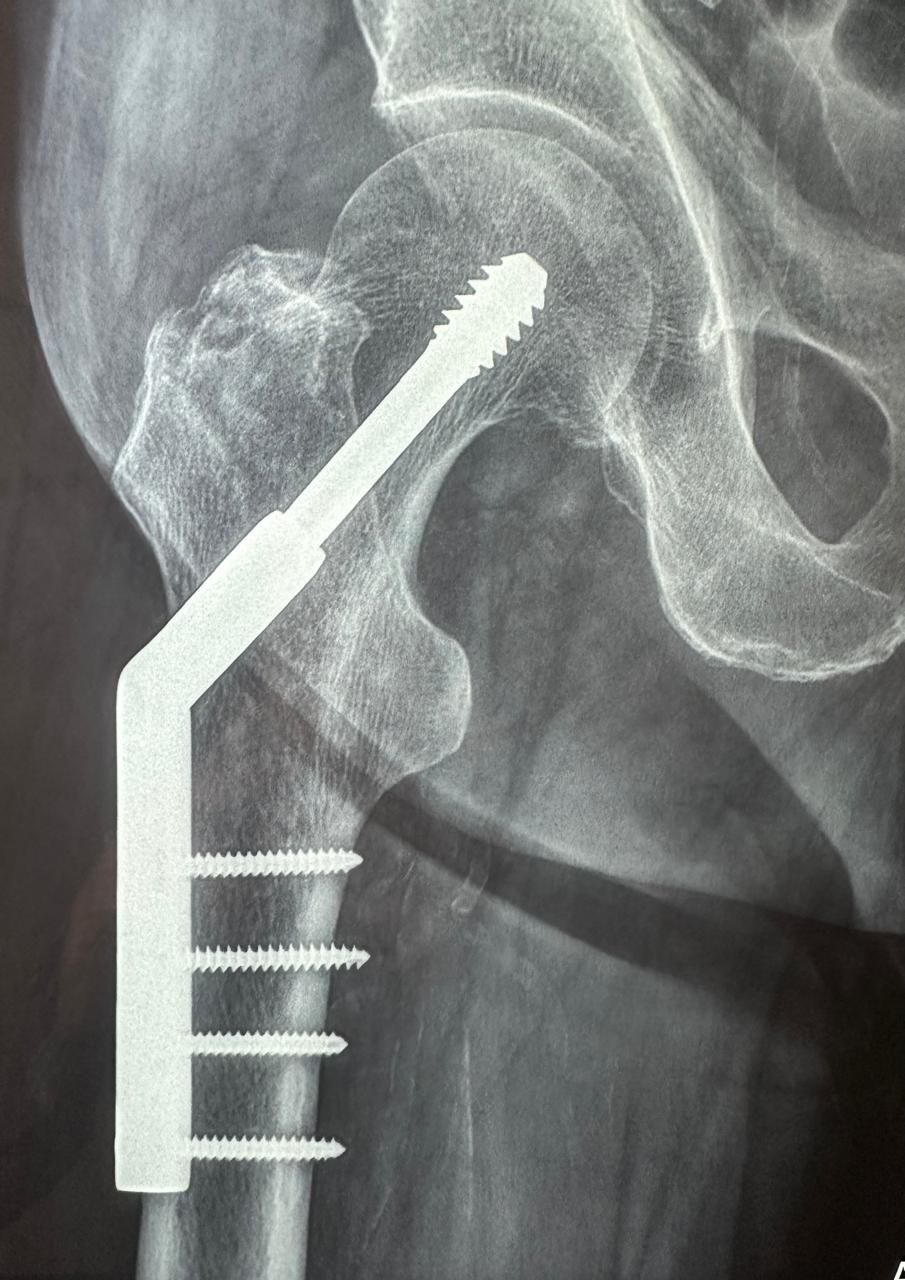

Cada caso es valorado a profundidad para proponer tratamientos conservadores (rehabilitación, ejercicios, ortesis) o procedimientos quirúrgicos cuando son necesarios, como artroplastías (colocación de prótesis articulares) o cirugías mínimamente invasivas como la artroscopía.